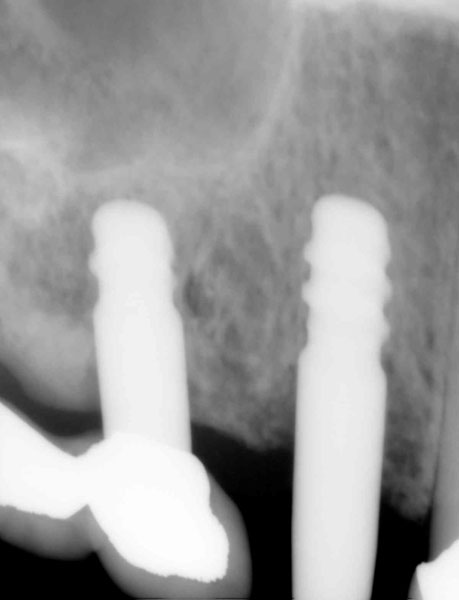

「10DR」とは、口腔内のCT画像を解析し、インプラント手術のシミュレーションを行うソフトです。

当院では「10DRインプラントシステム」を使用し、実際の手術の方法と手順を患者様にご説明いたします。

- まずレントゲンなどによる十分な診断を行い、治療の計画について説明をします。

- 歯の抜けたところへインプラントを植え込んだあと、あごの骨にしっかり固定されるまで、3〜6ヶ月待ちます。